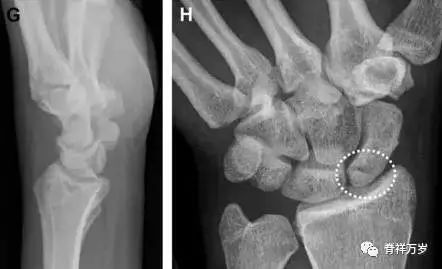

31.舟状骨骨折

舟状骨骨折 60%~70% 发生于腰部,15% 发生于近极, 10% 发生于远极, 8% 发生于远端关节面。除了常规的前后位、侧位、斜位片外,还需要拍专门的舟状骨位片(腕关节尺偏,以舟状骨为中心的腕关节前后位片),特别是鼻烟壶有压痛时。

图 2 舟状骨骨折 (A、B)第 1 例患者,舟状骨远极关节内骨折(白色箭头),斜位片显示较清楚(B);(C、D)第 2 例患者,舟状骨腰部骨折(虚线箭头),斜位片显示较清楚(D);(E~H)第 3 例患者,舟状骨近极骨折,常规 X 线片均未看到骨折,而在舟状骨位片上才能见到骨折(虚线圆)。

36.腕关节不稳定与脆弱区

月骨周围脱位和月骨周围骨折脱位常发生于摔倒后手掌撑地,由过伸、轴向*力暴**所致。所谓的「脆弱区」包括桡骨茎突、大多角骨、舟状骨、头状骨近端、钩状骨近端、三角骨的月骨缘、尺骨茎突。

图 7 经舟状骨骨折月骨周围脱位(腕关节前后位、斜位、侧位)。(A,B)前后位、斜位示月骨腰部骨折(黑箭头),第 1、2 腕弧中断,舟状骨近极(*)仍在原位,而远极(虚线)背侧脱位。